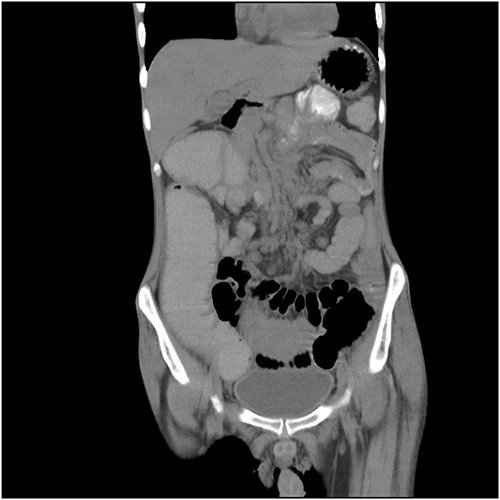

Blood tests, a 12-lead electrocardiogram, a chest X-ray and an abdominal X-ray were conducted in light of the ongoing abdominal pain, but the results were unremarkable. Additionally, pre- and post-contrast CT of the pelvis and abdomen was performed in a variety of planes and settings. After administering oral and intravenous contrast, it was seen that the proximal small bowel loops were dilated along with an ileo-ileal intussusception in the midline in the hypogastric region and jejuno-jejunal intussusception in the lumbar region. Figure 1 shows a CT coronal picture of the abdomen and pelvis that illustrates an intussusception and dilated loops. A spherical mass referred as ‘target-like lesion/donut-like lesion’, which is indicative of intussusception, is also seen in the CT axial image as seen in Fig. 2.

CT coronal picture of the abdomen and pelvis, illustrating dilated loops and intussusception.